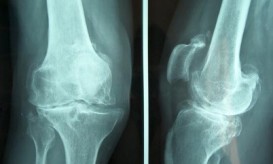

Γνωρίζετε τι είναι η οστεοαρθρίτιδα; Πως προσβάλλει και καταστρέφει κυρίως το ισχίο και τα γόνατα; Ποιους ανθρώπους “προτιμά” και...